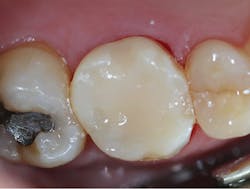

A final impression was made using a base VPS impression material (V-Posil Putty Fast, Voco; figure 11) followed by a light-body VPS impression material wash (V-Posil Light Fast, Voco; figure 12). A provisional crown was made using a cold-cure composite provisional material (Structur 3, Voco; figures 13 and 14) andcemented. The patient was dismissed. Upon return three weeks later, the provisional was removed and the definitive laboratory-fabricated zirconia crown was delivered.

Figure 14: Provisional crown